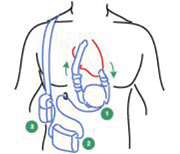

Flow sensors are common in Ventricular Assist Devices (VAD). The VAD is a mechanical pump assisting the heart by pumping blood to the rest of the body for patients with congestive heart failure. The VAD is typically made up of three sections (Fig. 6):

- The pump: May be placed inside or outside the body and is connected to the heart via a tube. Blood will travel from the heart, like in a healthy heart, down the inflow tube into the VAD. The VAD performs the heart function of pumping the blood to an outflow tube to a major blood vessel on its way back to the heart.

- The controller: This device is usually placed outside the body and controls the VAD by measuring airflow to be sure the correct amount is delivered to the pump that drives the flow of blood through the heart.

- The energy source: Again, this is typically outside the body and is either an AC power adapter or a battery pack to power the pump.